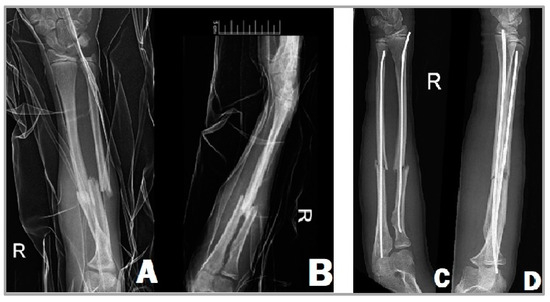

2.4. Operative Technique with Elastic Stable Intramedullary Nail (ESIN)

2.5. Operative Method with Resorbable Intramedullary Nail (RESIN)